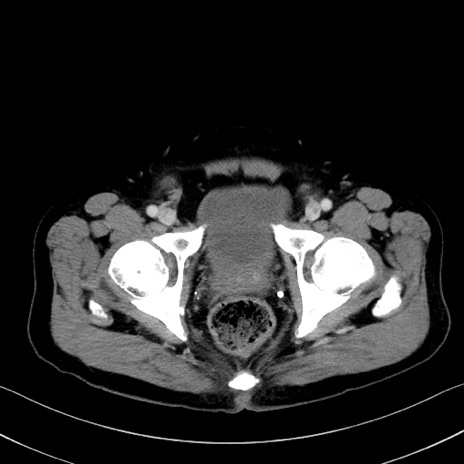

症例35(横断像)

【症例】70歳代 男性

【主訴】腹部膨満、嘔吐

【現病歴】昨日より腹部膨満感出現。本日増悪し、仙痛出現。嘔吐あり、受診。

【既往歴】糖尿病、胆摘後

【身体所見】BP 149/80mmHg、HR 74/min、BT 35.9℃、腹部:膨満、軟、圧痛なし。腸雑音減弱あり。上腹部正中切開瘢痕あり。

【データ】WBC 13500、CRP 1.72